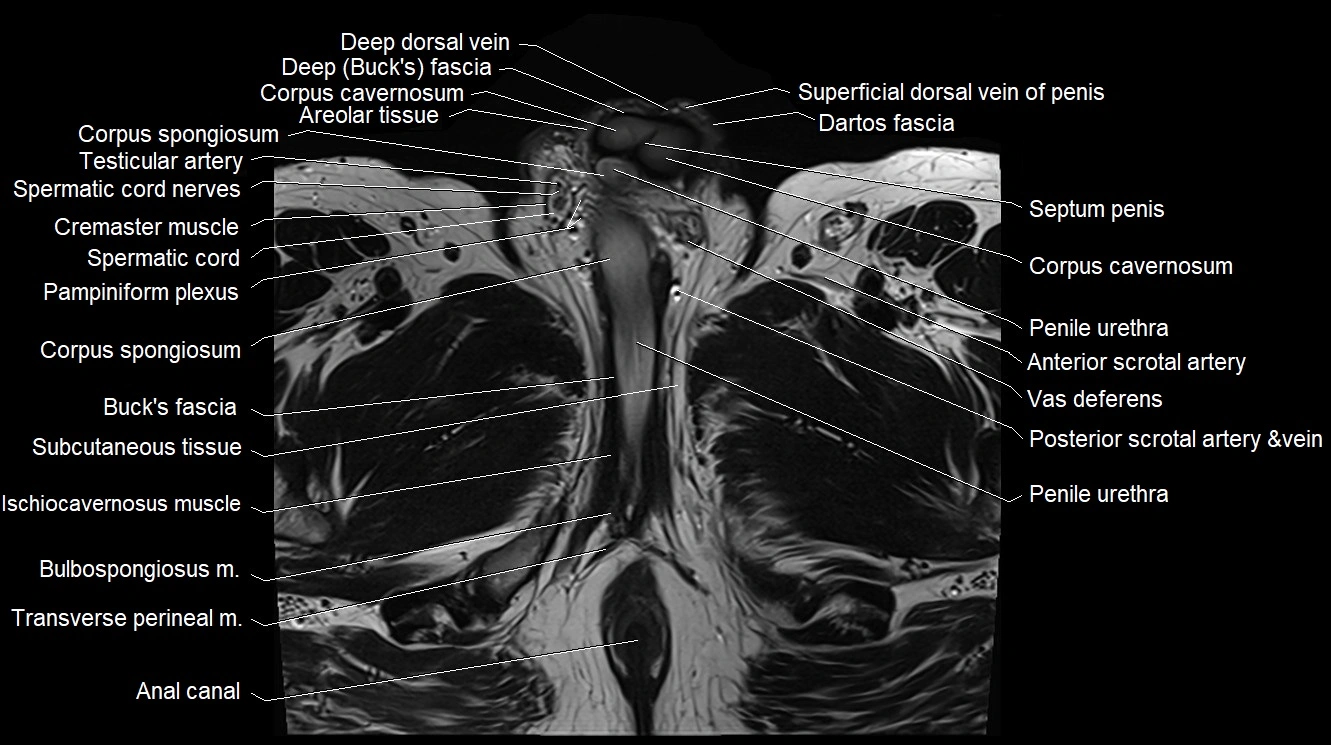

- Anal canal

- Areolar tissue of penis

- Buck's fascia (Deep fascia of penis)

- Bulbospongiosus muscle (Male)

- Corpus cavernosum

- Corpus spongiosum

- Cremaster muscle

- Dartos fascia

- Deep dorsal vein of penis

- Deep dorsal vein of the penis

- Pampiniform plexus

- Penile urethra

- Spermatic cord

- Spermatic cord nerves

- Testicular artery

- Transverse perineal muscle